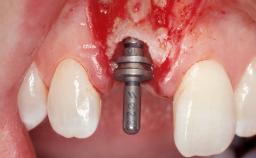

Immediate Flapless Placement of an Implant in a Maxillary Right Lateral Incisor Site

This 43-year-old male patient, a non-smoker, came to our practice because of a fracture of tooth 12 caused by a bicycle accident. Due to the combined para- and infrabony crown and root fracture, tooth extraction, and subsequent implant placement were suggested to the patient as the therapy of choice. The patient had high esthetic expectations with regard to the treatment outcome and asked for an immediate fixed provisional restoration. His individual esthetic risk profile summed up to a medium esthetic risk.

Placement Protocol Immediate implant placement

Tooth Site Maxillary incisor or canine

Loading Protocol Immediate

Provisional Implant-Supported Prosthesis Prosthodontic margin > 3 mm apical to mucosal margin Prosthodontic margin > 3 mm apical to mucosal margin